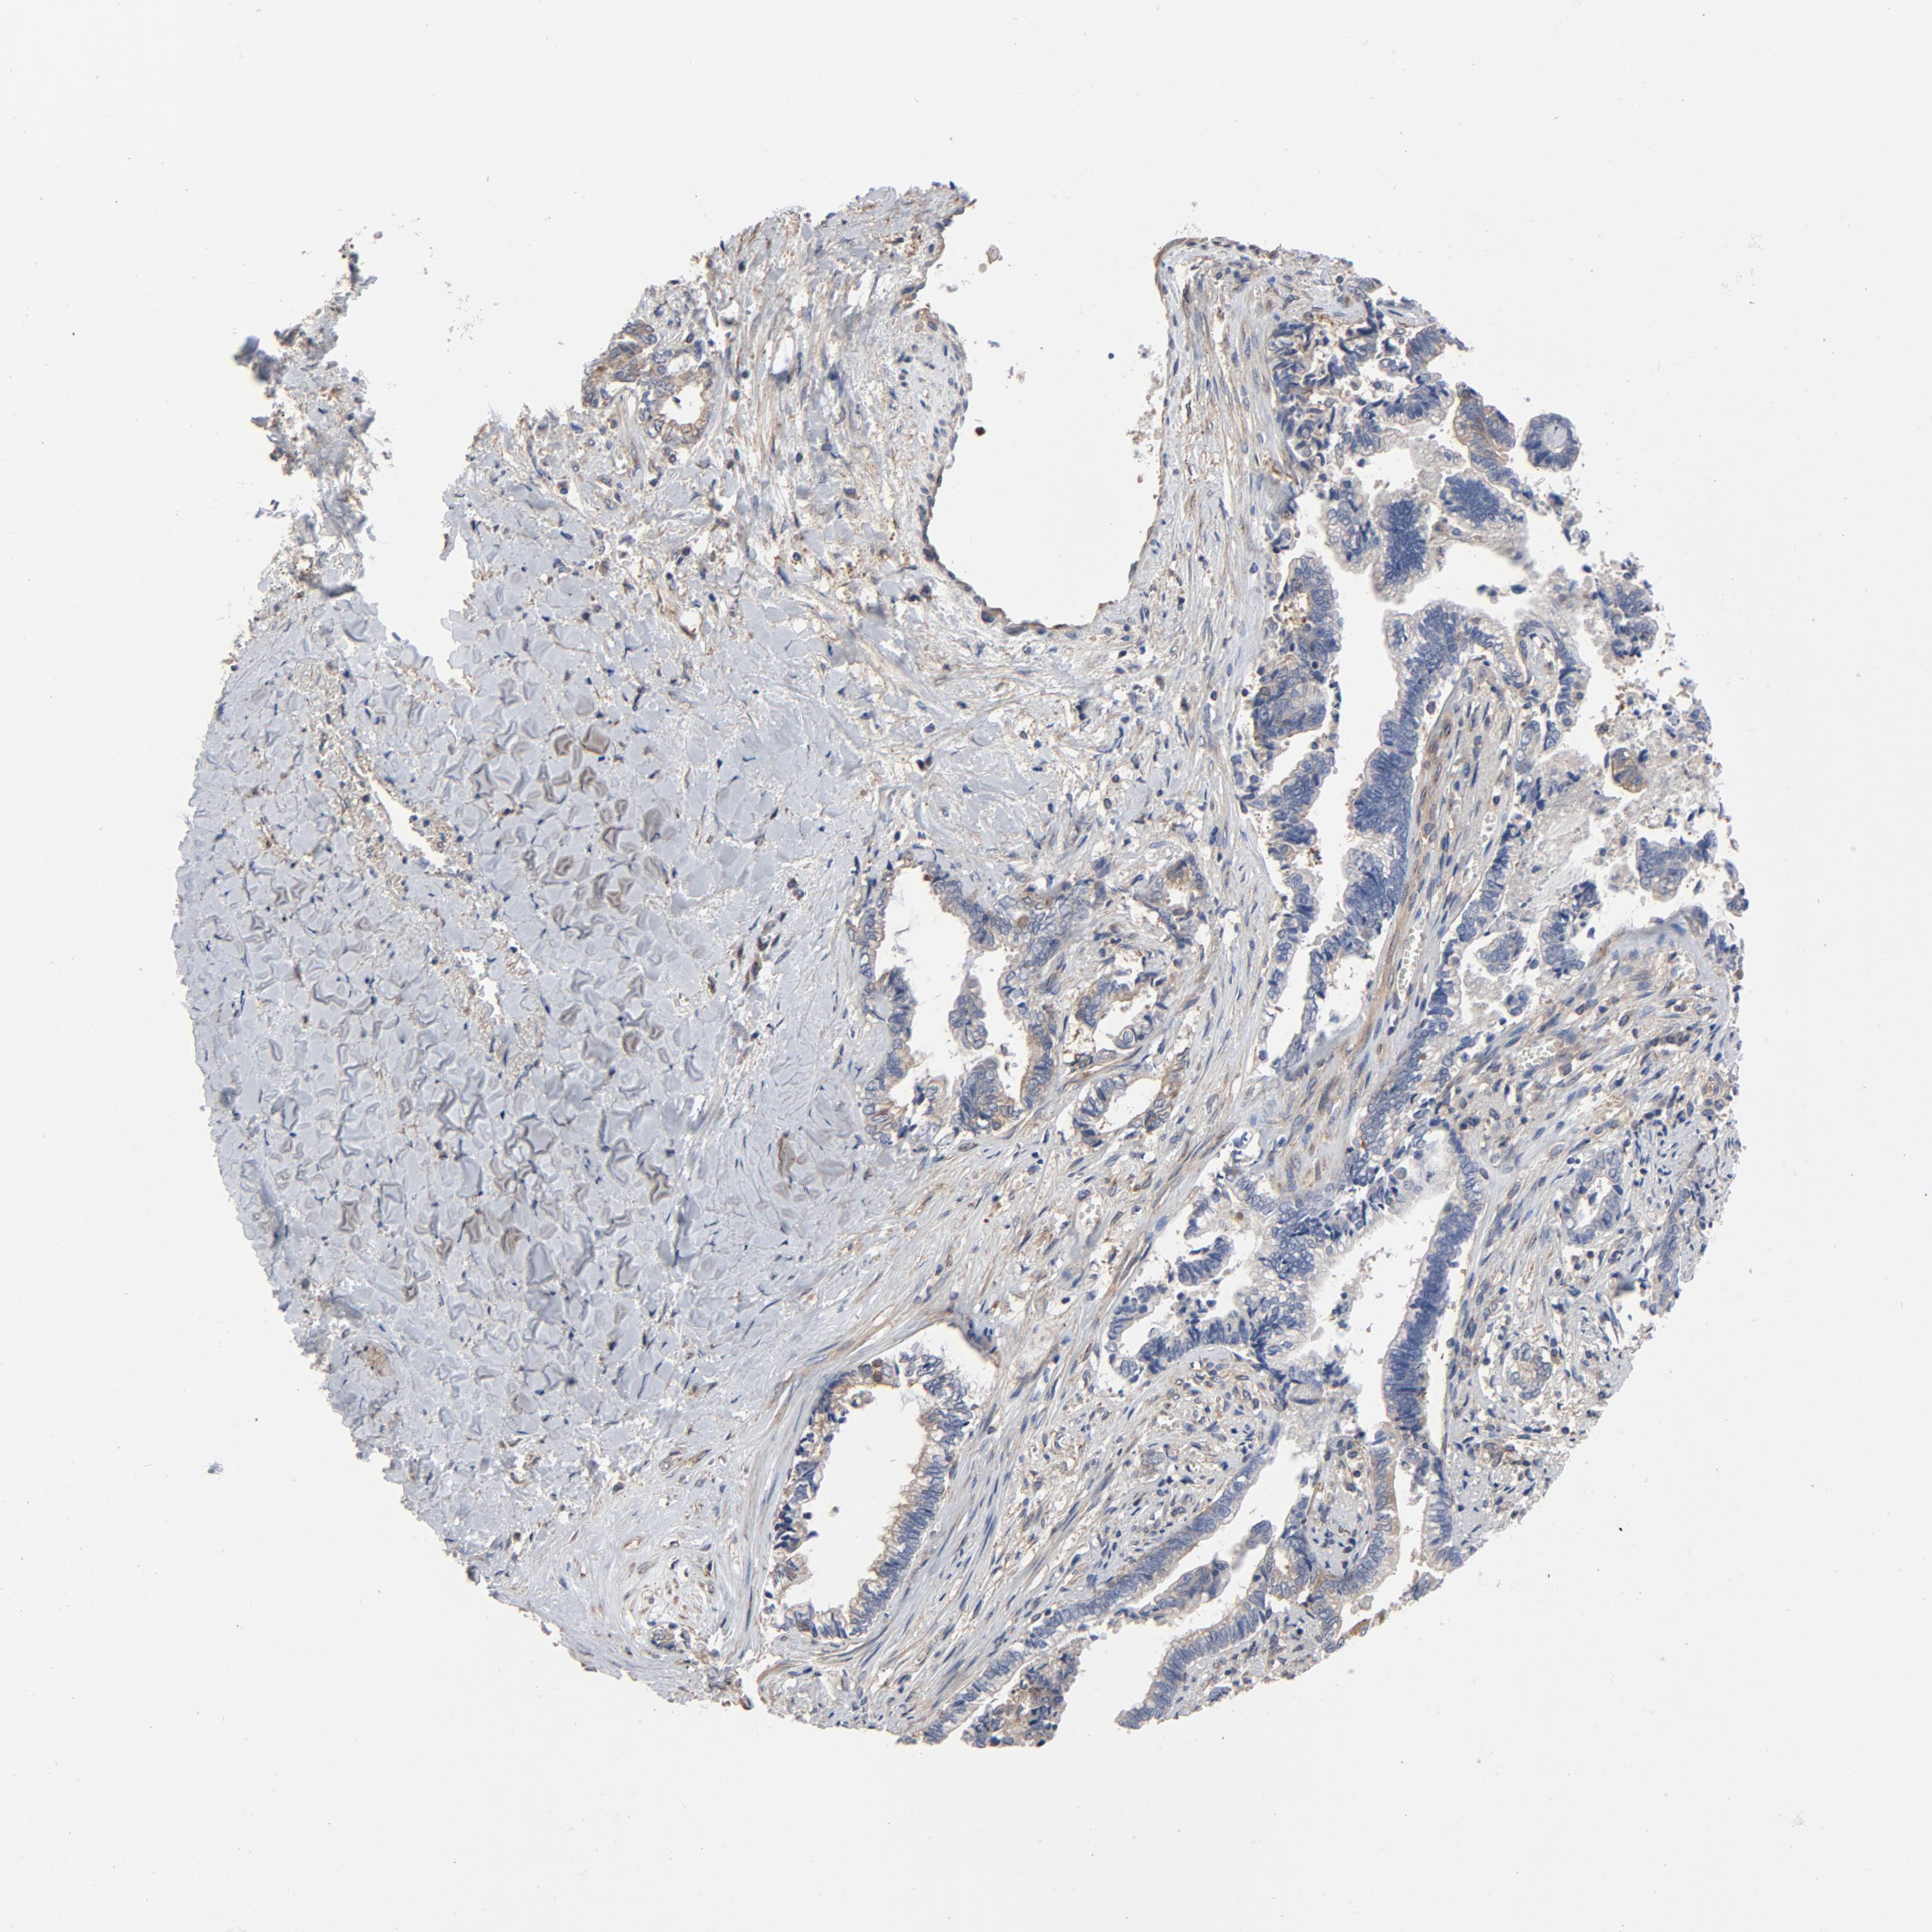

LIVER CANCER - Protein expressioni

A mouse-over function shows sample information and annotation data. Click on an image to view it in a full screen mode. Samples can be filtered based on level of antibody staining by selecting one or several of the following categories: high, medium, low and not detected. The assay and annotation is described here.

Note that samples used for immunohistochemistry by the Human Protein Atlas do not correspond to samples in the TCGA dataset.

Antibody stainingi

Antibody staining in the annotated cell types in the current human tissue is reported as not detected, low, medium, or high, based on conventional immunohistochemistry profiling in selected tissues. This score is based on the combination of the staining intensity and fraction of stained cells.

Each image is clickable and will lead to virtual microscopy that enables deeper exploration of all samples and also displays staining intensity scores, fraction scores and subcellular localization as well as patient and tissue information for each sample.

Antibody HPA003938

Staining

High

Medium

Low

Not detected

Intensity

Strong

Moderate

Weak

Negative

Quantity

>75%

75%-25%

<25%

None

Location

Nuclear

Cytoplasmic/membranous

Cytoplasmic/membranous,nuclear

Cholangiocarcinoma

Carcinoma, Hepatocellular, NOS